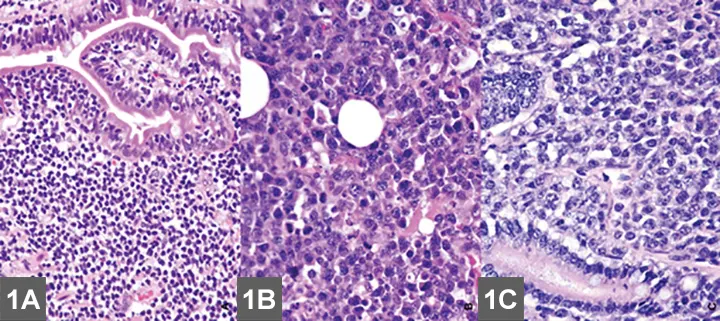

• EATL type I is typically a straightforward histologic diagnosis.1,5-7

• EATL type II can be more difficult to confirm; it must be histologically differentiated from IBD (Figure 6, see gallery).1,5-7

• Characteristics more suggestive of EATL II over IBD include the presence of lymphoid infiltration beyond the mucosal layer, the presence of epitheliotropism, and certain characteristics of neoplastic lymphocytes.1,5-7

• Distinction can still be difficult without more advanced histologic techniques (see Table); how the biopsy is obtained is controversial.1,5-7